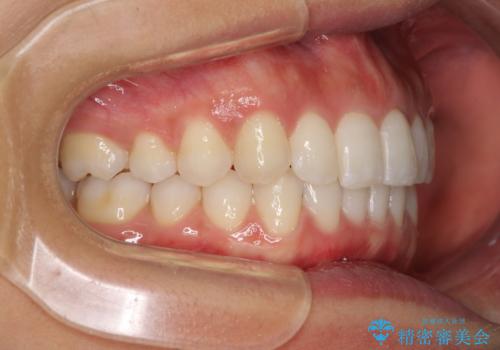

- 深い咬み合わせ(ディープバイト)と前歯のデコボコを気にして来院された患者様です。

インビザラインによる上下歯列の側方拡大と後方移動、IPR(歯と歯の間を削る)にるスペースの獲得により、デコボコとディープバイトを改善することとしました。

1日22時間の装着時間をしっかり守ってくださったので、予定通り1年で治療を終えることができました。

ディープバイトによる食いしばり癖も解消され、患者様には大変満足していただきました。